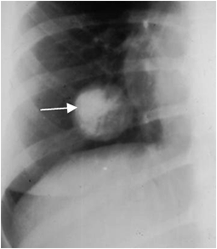

Fig 72. Metástasis osteosarcoma.

Rx PA. Lesión redondeada y con calcificación excéntrica, que corresponde a metástasis de un osteosarcoma.